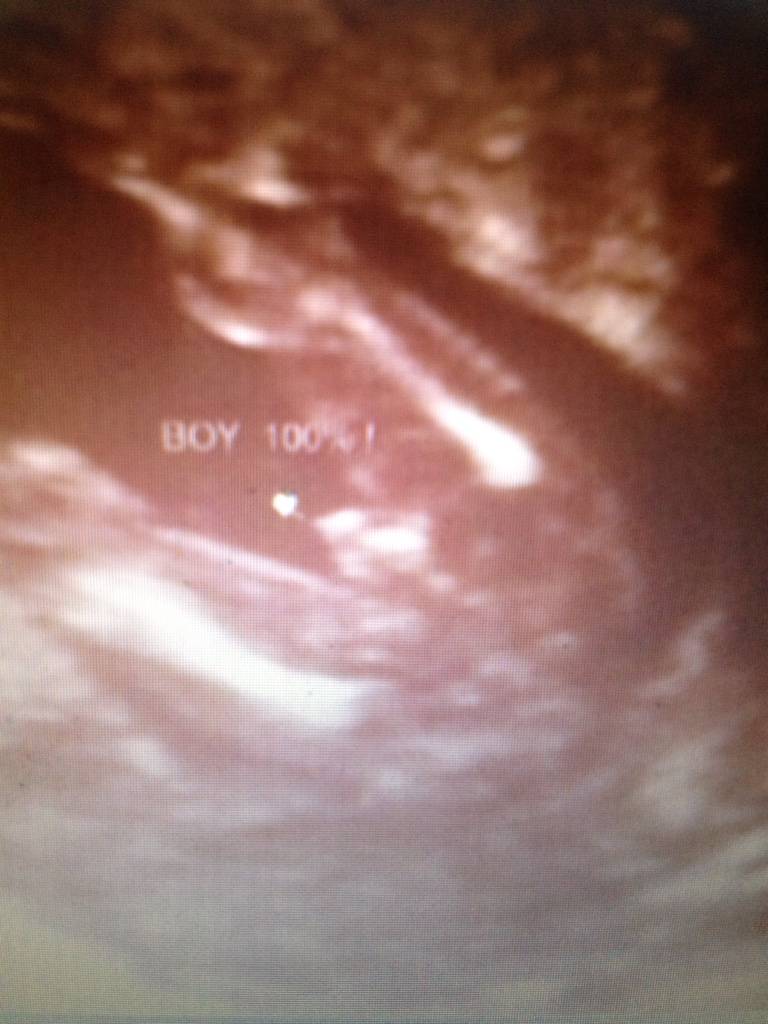

Witam w 19 tygodniu ciąży dowiedziałam się ze będę miała dziewczynkę w 20 tyg okazało się jednak , że to chłopak. Sama już nie wiem bo na jednym usg widać na pewno dziewuche a na drugim chłopca. Może to pempowina ?? Może ktoś mi pomoże rozwiązać ta zagadkę

Załączniki

• 4A8F5FF1-76CA-4DE0-AC12-5EDF08E820F2.jpg

4A8F5FF1-76CA-4DE0-AC12-5EDF08E820F2.jpg

596,4 KB · Wyświetleń: 43 671